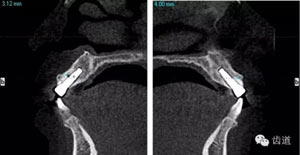

術(shù)前放射片

術(shù)后CT

戴牙后CT